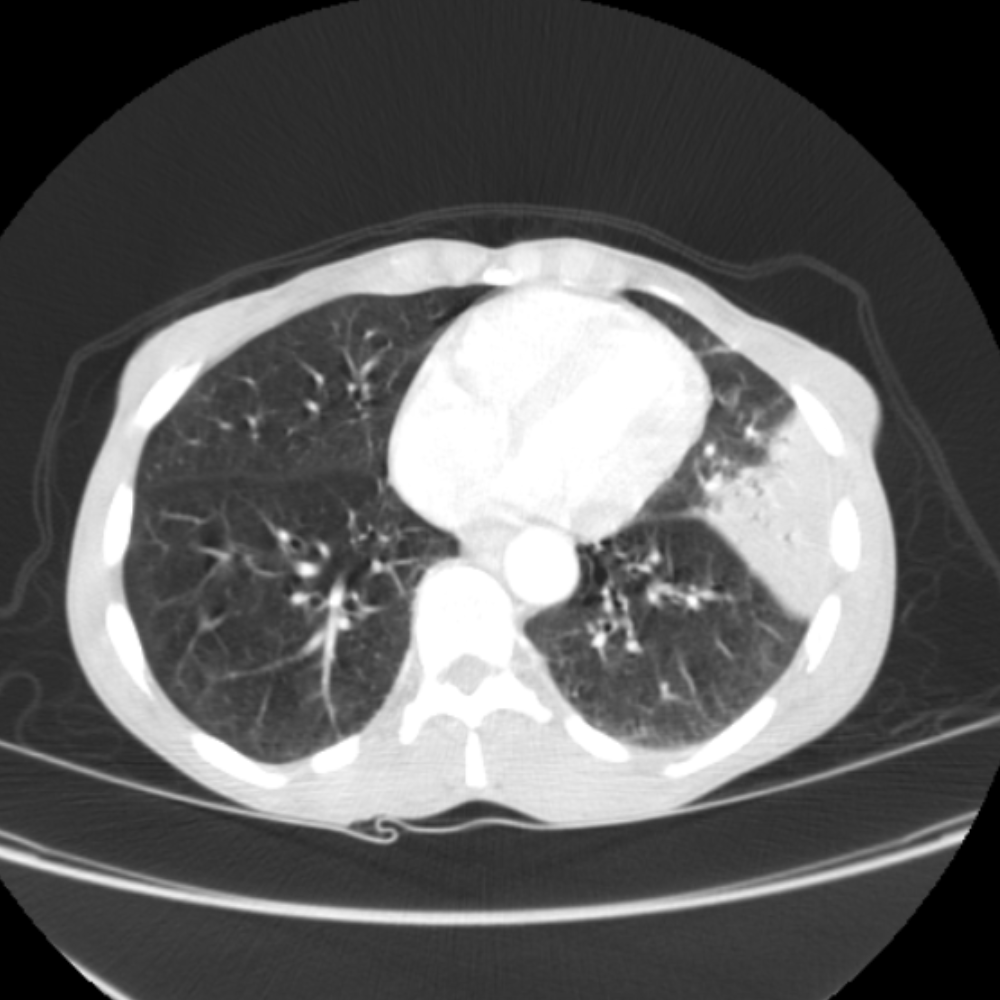

Practice Chest CT Cases for Radiologists Chest Radiology Cases learn & practice radiology. Clinical cases and self assessment problems to enhance interpretation skills through ct scan interpretation in clinical. Knife penetrates through the lateral left manubrium and extends into the prevascular space. the education committee of the str is pleased to present the case of the month in thoracic and cardiac imaging. browse chest radiology cme. Chest Radiology Cases.